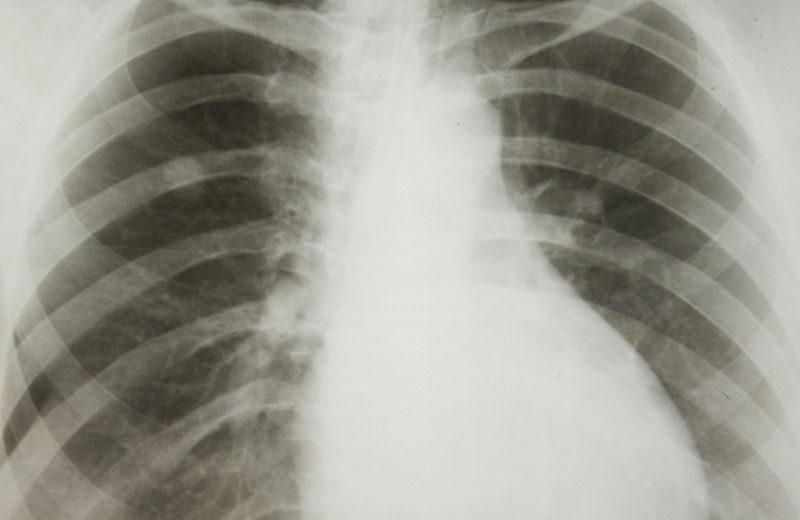

There is a new first-line therapy which helps people with advanced non-small-cell lung cancer (NSCLC). Its name is platinum-based chemotherapy and it lacks any targetable mutations. The pembrolizumab substance has recently replaced the cytotoxic chemotherapy as the first-line treatment. This addition brought a dramatic increase in the positive response. Moreover, there was a longer progression-free survival rate than when the doctors used only chemotherapy.

The study was, in fact, a double-blind, phase 3 trial. The scientists initially randomly assigned 616 patients that had metastatic nonsquamous NSCLC to get a platinum-based drug, pemetrexed, plus a placebo or 200 mg of pembrolizumab every 3 weeks.